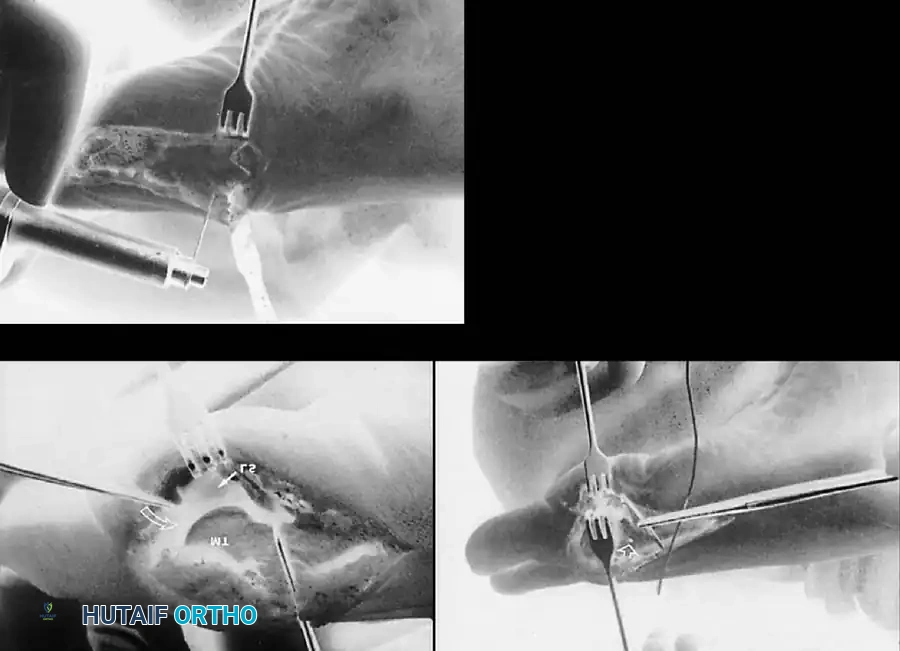

• Grasp the hallux in one hand and displace the proximal remnant medially so that, under direct vision, two longitudinal 0.062-inch Kirschner wires can be inserted.

• Hold the interphalangeal joint straight while drilling the wires from proximal to distal, emerging a few millimeters plantar to the nail plate.

• Return the foot to the corrected position, and drill the wires into the metatarsal head.

• While holding the metatarsal as far laterally as possible, cross the joint, and drive the wires out the plantar cortex just proximal to the head, while holding the hallux in 10 to 15 degrees of extension, neutral abduction, adduction, and rotation, and no translation dorsally or plantarward on the metatarsal head. The wires should penetrate only 2 to 3 mm past the cortex to avoid tenderness over the wires with weight bearing.

• If the Kirschner wires tend to “walk” on the rounded articular surface of the metatarsal head, use a small hemostat snugged up against the wire while it is being drilled to allow accurate placement. Proper placement of the wires and the desired position of the hallux on the metatarsal may require several attempts. The medial aspect of the proximal phalanx should not rest medial to the medial aspect of the metatarsal head.

• Using a Freer elevator or a small osteotome for its strength, mobilize the fi bular sesamoid (Fig. 78-31A to C). This may be diffi cult in elderly patients with signifi cant deformity and adherence of the sesamoid to the metatarsal head. Lift the metatarsal dorsally for exposure (Fig. 78-31D and E).

• When the sesamoid has been removed, insert two 0.062-inch Kirschner wires retrograde from the tip of the toe 2 to 3 mm plantar to the nail bed, leaving about 5 to 7 mm of the pins exposed at the base of the phalangeal remnant to help align the phalanx on the metatarsal before antegrade passage of the pins into the metatarsal (Fig. 78-31F).

Fig. 78-31 Excision of fi bular sesamoid in modifi ed Keller procedure. With base of proximal phalanx removed and medial eminence excision, exposure of fi bular sesamoid is not as diffi cult from medial incision. A, Operative photograph showing elevation of fi rst metatarsal with strong two-tooth retractor and use of small osteotome to mobilize fi bular sesamoid and lateral capsuloligamentous (frequently contracted) structures. Osteotome is between metatarsal head and lateral sesamoid. When mobilization of fi bular sesamoid is complete, entire sesamoid is visible for excision. Note chondromalacia of tibial sesamoid articular surface medial to osteotome. B, Fibular sesamoid has been excised, and lateral capsular structures and conjoined tendon (in forceps) have been released. Neurovascular bundle to lateral side of hallux is adjacent to these structures. C, Diagrammatic representation of modifi ed Keller procedure. By excising fi bular sesamoid, valgus moment of conjoined tendon of fl exor hallucis brevis and adductor hallucis no longer pulls fl exor hallucis longus tendon laterally (carrying hallux with it) through capsulosesamoid plantar plate and pulley system. D, Metatarsal head must be lifted dorsally to excise fi bular sesamoid under direct vision. E, Note exposure of fi bular sesamoid after mobilization of metatarsal head. Continued

F G

H I

J

Fig. 78-31, cont’d F, Two 0.062-inch Kirschner wires are drilled distally. G, First metatarsal head is manually displaced laterally, and hallux is placed end-on the fi rst metatarsal. Kirschner wires are drilled proximally across joint. H, Capsule is mobilized dorsally and plantarward. I, 2-0 or 3-0 absorbable sutures placed in purse-string fashion are used for capsular closure. J, Capsule must be closed over joint. Note pins cut off at skin level; they also can be bent at skin level.